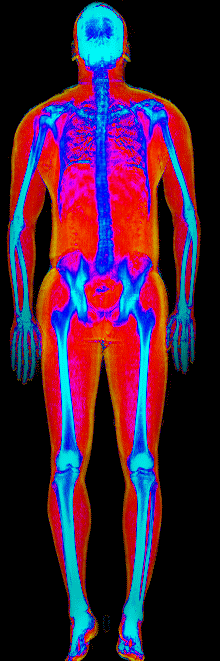

What Muscle Gain Looks Like on a DEXA Scan

Gained 12.0 lb lean, lost 24.9 lb fat · 183 → 170 lb · Age 37

Gained 10.0 lb lean · 140 → 152 lb · Age 23